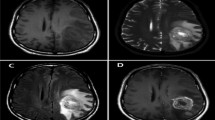

Brain tumors are one of the leading causes of death worldwide. Different types of brain tumors are known, so the choice of treatment depends directly on the type of tumor. The classification of brain tumors is very important as a complex and challenging problem in the field of image processing. Today, deep learning methods are used to classify brain tumors. In addition to being able to detect and automatically classify all types of brain tumors, these methods significantly reduce the diagnosis time and increase accuracy. In this paper, a deep learning-based model is proposed to classify brain tumors into three classes: glioma, meningioma, and pituitary tumor. In the first phase, the pre-trained network ResNet50 is used to extract features from MRI images. In the second phase, by proposing two attention mechanisms (depth-separable convolution-based channel attention mechanism and an innovative multi-head-attention mechanism), the most effective spatial and channel features are extracted and integrated. Finally, the classification phase is performed. Evaluations on the Figshare dataset showed an accuracy of 99.32%, which performs better than existing models. Therefore, the proposed model can accurately classify brain tumors and help neurologists and physicians make accurate diagnostic decisions.